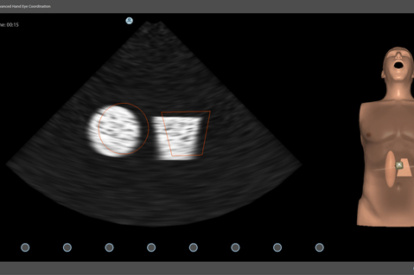

Simbionix Ultrasound Mentor is the answer to the growing need for ultrasound training among multiple medical specialties. This modular simulation platform enables easy manikin rotation (male, female, pediatric and interventional), and offers diverse applications for a range of specialties such as OB/GYN, Point-of-care Ultrasound (POCUS) and Echocardiography.

Ultrasound Mentor accelerates the development of basic to advanced technical and cognitive skills, by providing not only the probe manipulation training, but also a didactic environment enabling structured, self-guided learning including step-by-step instructions and educational aids such as 3D anatomical map and probe positioning assistant, all backed up with our progress monitoring tool MentorLearn.

- An immersive learning experience with VR goggles and a designated probe add-on